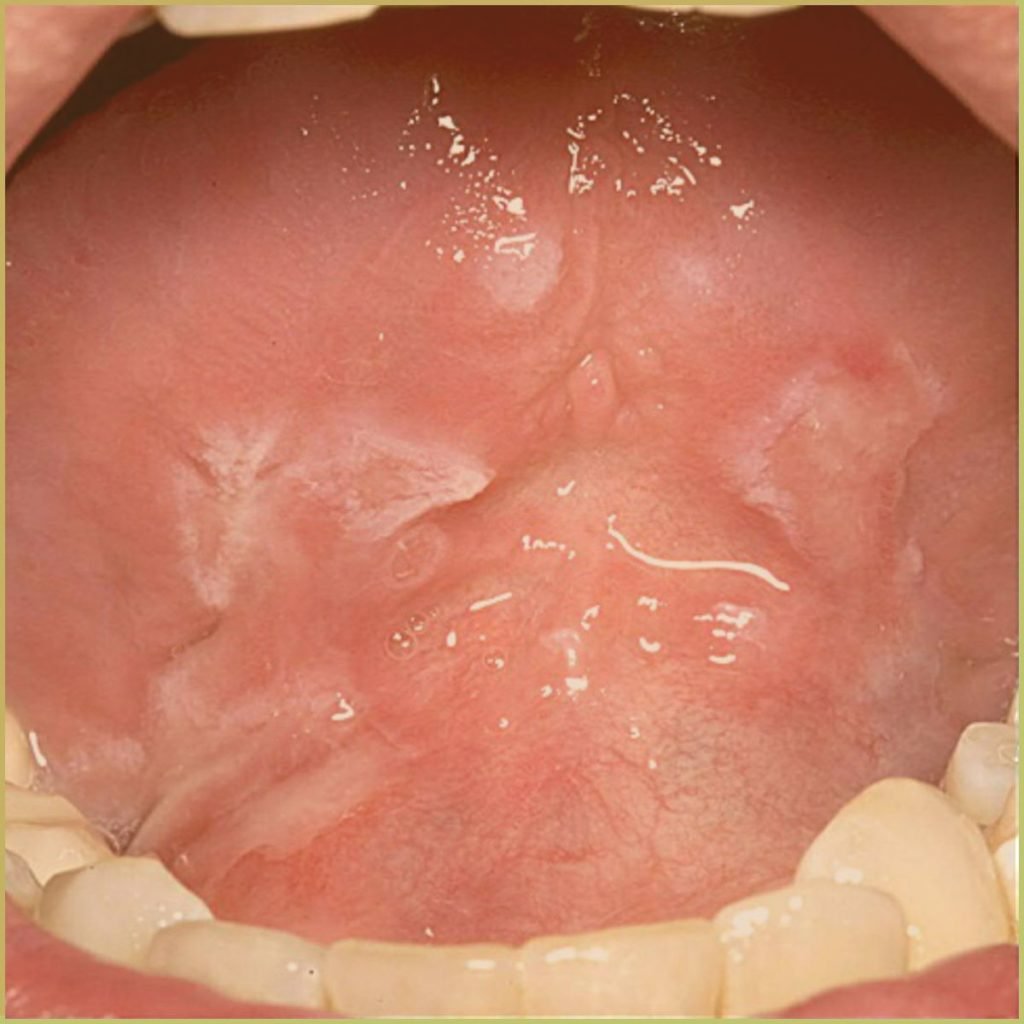

PEMPHIGUS VULGARIS

Pemphigus Vulgaris is a rare auto-immune disorder (type II hypersensitivity reaction) caused by antibodies directed at the desmosome-related proteins desmoglein 3 or desmoglein 1. This leads to acantholysis (loss of intercellular cohesion) and subsequent subepidermal blister formation. The common clinical presentation includes:

- Nikolsky’s sign (slight rubbing of the skin results in exfoliation of the outermost layer).

- Painful, shallow irregular ulcers with friable adjacent mucosa.

- Multiple intraoral sites including keratinized and non-keratinized tissue.

- Can present with cutaneous blisters, as well as blistering on other mucosal surfaces (conjunctiva, nose, esophagus).

Diagnosis is based on the lesion history, clinical presentation and microscopic findings, which may include:

- Tzanck cells – large, rounded keratinocytes with a hypertrophic nucleus.

- Acantholysis between suprabasal and basal layer of epithelium.

- Vesicle forms at site of epithelial split.

- IgG and complement deposition in intercellular spaces.

- Direct immunofluorescence examination positive in all cases.

- Indirect immunofluorescence examination positive in most cases.

Your differential diagnosis should include:

- Mucous membrane pemphigoid.

- Erythema multiforme.

- Erosive lichen planus.

- Lichenoid drug reaction.

Treatment options include:

- Topical corticosteroids.

- Systemic corticosteroids (prednisone) or other immunosuppressive medications.

- Azathioprine or cyclophosphamide.

- Tetracycline/niacinamide.

- Dapsone (antibiotic).